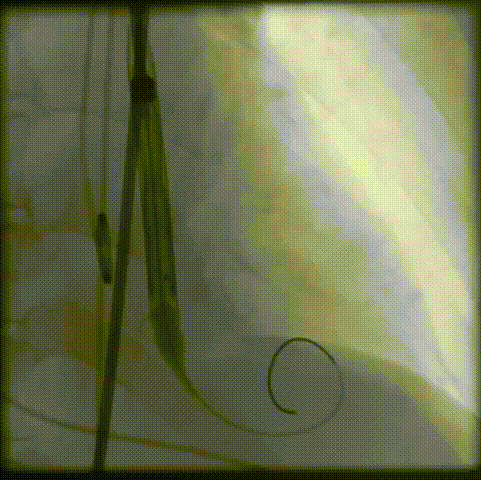

主动脉根部造影

输送器顺利过弓、跨瓣

瓣膜标准位定位

瓣膜释放到工作位

工作位造影

位置理想,瓣膜完全释放

释放后造影

外周造影无狭窄闭塞